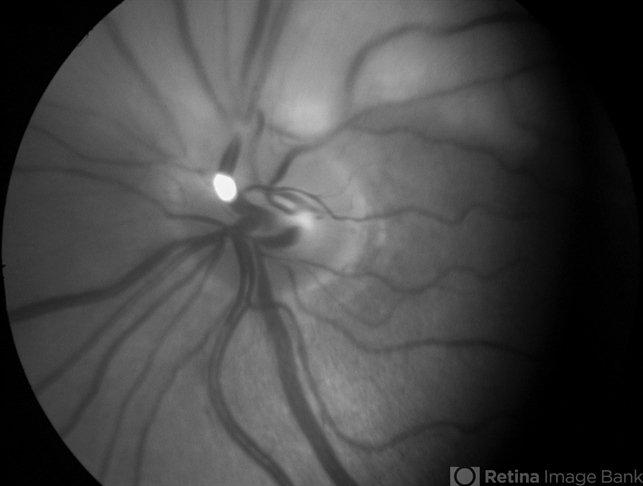

- hollenhorst plaque, red-free

- Hollenhorst plaque shining in the red free image of a patient with superior branch retinal artery occlusion.